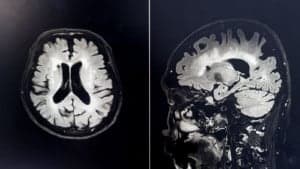

The brain is our most precious possession. Without it, we couldn’t think, feel, or act. The brain is what permits us to communicate, make decisions, and plan. It’s what makes us, well, us.

But the harsh truth is that many of us don’t think much about our brain until something goes wrong.  We can’t see it or feel it, and despite being the center of our sense perceptions, it is by itself imperceptible. It gets much less attention than, say, the heart (which is perceptible via feeling.)  As a result of these qualities, we sort of take the brain for granted.

Neuroplasticity is a combination of two words: neuro, “relating to nerves or the nervous system,” and plasticity, “the quality of being easily shaped or molded.” The term neuroplasticity, therefore, means the moldability or malleability of the nerves in the brain.

As mentioned, it’s the nerve cells (neurons) of the brain which are capable of changing. The factors that stimulate such changes can be behavioral, biological, or environmental in nature. For example, the neuronal structure can alter due to trauma (environmental), disease (biological), or chronic stress (behavioral).

A critical part of neuroplasticity is a process called synaptic pruning. Synaptic pruning is the elimination of extra synapses – junctions between neurons – that occurs naturally when brain structure alters. This process occurs most rapidly between early childhood and adulthood and is crucial for more efficient brain function. For example, synaptic pruning enables to learning and retainment of new and complex information.

White matter differs from the more-well-known grey matter. The former is comprised of long nerve fiber clusters that conduct electrical signals across different brain regions. The latter is made up of the neuronal bodies responsible for the heavy computation and processing in the brain.